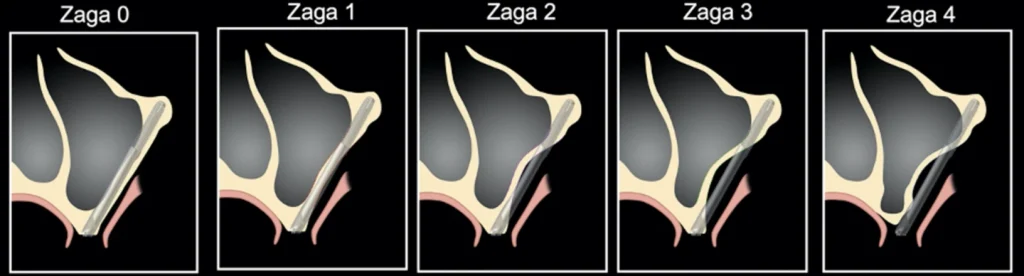

La classification ZAGA

La classification ZAGA est une description squelettique anatomique maxillo-zygomatique décrite par le Dr Aparicio. En fonction du volume osseux du complexe zygoma-maxillo-alvéolo-crestal, l’implant aura un placement et trajet différent.

ZAGA 0 :

La paroie antérieure du sinus est plate, le col de l’implant est dans l’os de la crête alvéolaire. Le corps de l’implant est intra-sinusien.

ZAGA 1 :

La paroie antérieure du sinus est légèrement concave, le col de l’implant est dans l’os alvéolaire crestal, le corps de l’implant est principalement intra-sinusien. Il est visible à travers la paroie osseuse sinusienne.

ZAGA 2 :

La paroie antérieure du sinus est concave, le col de l’implant est dans l’os alvéolaire crestal. Le corps de l’implant est principalement extra-sinusien.

ZAGA 3 :

La paroie antérieure du sinus est très concave, le col de l’implant est dans l’os alvéolaire crestal. Le corps de l’implant est totalement extra-sinusien sans contact avec la concavité de la paroie antérieure du sinus.

ZAGA 4 :

Le maxillaire et l’os alvéolaire présentent une atrophie extrême. Le col de l’implant est vestibulé extra-osseux, le corps de l’implant est extra sinusien, l’ancrage de l’implant se fait seulement au niveau du zygoma.